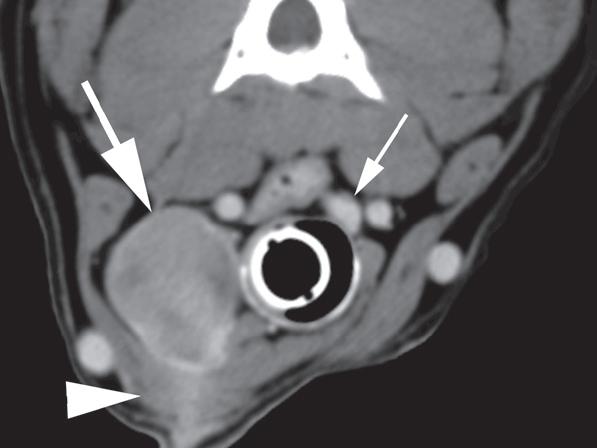

Rycina 1.11.6. Rak tarczycy i gruczolak tarczycy (pies) TK

Badanie wykonano u 12-letniej, kastrowanej samicy owczarka australijskiego z prawostronną masą w dobrzusznej części szyi. Badanie USG wykazało dużą, litą, unaczynioną masę w obrębie prawego płata tarczycy (a) oraz mniejszą, hipoechogeniczną masę w obrębie lewego płata (b). Obrazy TK przed i po podaniu środka kontrastowego (c–f) ułożone od doczaszkowych do doogonowych ukazują dużą, prawostronną, jednorodnie wzmacniającą się masę (c–f – duża strzałka) z niewyraźną granicą dobrzuszną oraz pozatorebkowym szerzeniem się i rozlanym wzmocnieniem pokontrastowym przyległych tkanek (e, f – grot strzałki). W obrazie bardziej doczaszkowym widoczny jest prawidłowy lewy płat (c, e – mała strzałka), natomiast w obrazie bardziej doogonowym jest on powiększony i ma niższą gęstość, niż można by oczekiwać, co sugeruje obecność drugiej, mniejszej masy (d, f – mała strzałka). W obrazach reformowanych wzdłuż osi długiej widać dwa małe guzki w lewym płacie (h – małe strzałki). Wyniki obrazowe potwierdzono podczas zabiegu (i, j – strzałki). Biopsja wycinkowa wykazała prawostronnego raka tarczycy z naciekaniem pozatorebkowym oraz lewostronnego gruczolaka tarczycy